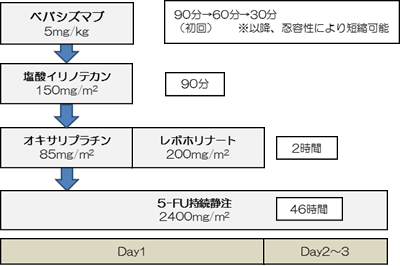

日本がん対策図鑑 | 【標準治療】大腸がん。日本がん対策図鑑 | 【標準治療】大腸がん。100F33 | 大腸癌, 転移性肝癌 国試 | テコプラ。S*i様 白酒 茅台酒 君作 53% 500ml。マーカー、断裁なし。上に押し印ありますので、消して発送します。目立った汚れはありませんが、あくまで中古品なのでご理解ある方ご購入お願いします。。腎盂・尿管・膀胱癌取扱い規約 第2版 – 医学図書出版。。【ピー】レジデントのための糖尿病・代謝・内分泌内科ポケットブック